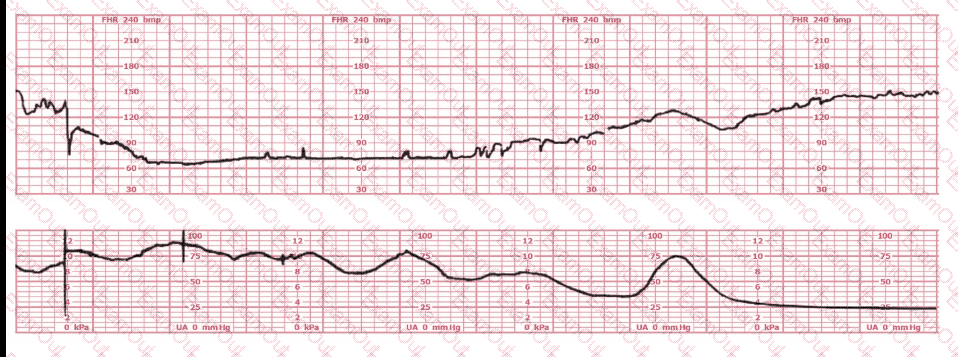

This fetal heart rate tracing is from a woman in the second stage of labor. This tracing is best interpreted as: